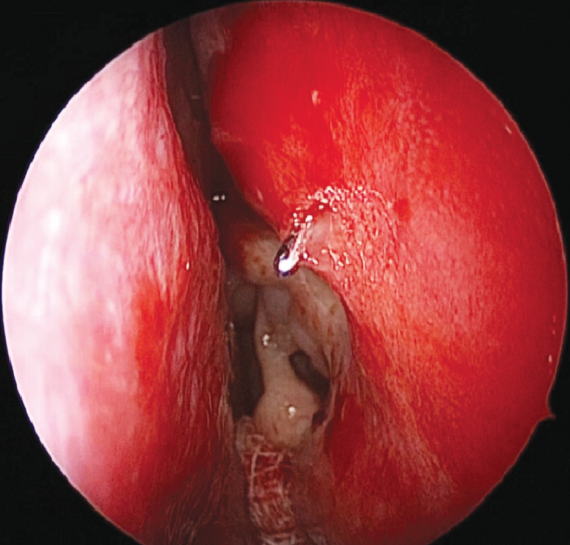

Fig. 2. Endoscopic view of scar tissue in the area of dacryostoma (left nasal cavity). The ostium was probed with Bowman probe

Рис. 2. Эндоскопическая картина области рубцово-изменнённой дакриостомы (левая половина носа). Зонд Боумена выведен через дакриостому

The intervention was performed as follows. Under local and conduction anesthesia with intravenous sedation, antegrade probing of the dacryostomy area was performed with the formation of an opening in the scar tissue (in three cases) and with probing of residual dacryostomy (in three cases; Fig. 2). Purulent discharge was removed from the lacrimal sac cavity using an aspirator. A balloon was inserted endonasally into the dacryostomy opening using a curved von Eicken cannula for irrigation with an outer diameter of 4.0 mm and length of 15 cm (Karl Storz, Germany; Fig. 3). Balloon dacryoplasty was performed according to the protocol we developed earlier in the experiment [8] and tested in the clinical setting (Fig. 4) [9]. The balloon was dilated at a pressure of 8 atm. for 90 s, and after 10 s, it was repeated for 60 s. After deflation, the balloon was removed. Figure 5 shows an enlarged dacryostomy after the intervention. A hemostatic sponge was inserted into the dacryostomy area, which was removed 48 h after the surgery.